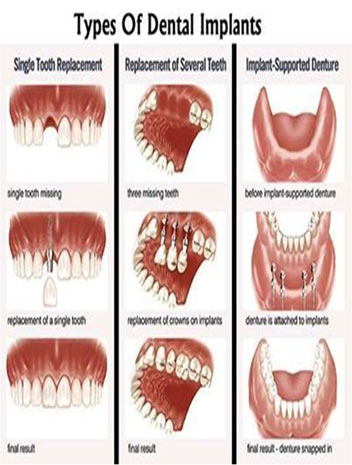

Oral and maxillofacial surgery deals with a variety of conditions associated with the mouth, jaws, face and neck. To become a consultant in oral and maxillofacial surgery, you need to be qualified in both medicine and dentistry. The combined medical, dental and surgical training reflects the broad nature of the work undertaken by oral and maxillofacial surgeons.

Orthognathic surgery involves the surgical manipulation of the elements of the facial skeleton to restore the proper anatomic and functional relationship in patients with dentofacial skeletal anomalies.

An oral surgeon is a specialist who has an expertise in performing surgeries related to teeth,mouth & structures adjoining it.Here is brief description of some common dental/oral surgeries performed by our expert oral surgeon.

Dr. Sukumar Singh can manage efficiently most aspects of Oral & Maxillofacial Surgery. He has a total experience of more than 11 years in academics as well as in private practice. He had placed more than 7000 implants which include advanced procedures like direct and indirect sinus lift procedures and nerve lateralization...